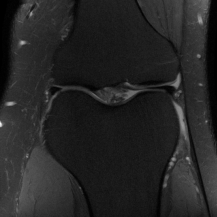

| Ground Truth | Global | LONDN-MRI | LONDN-MRI | Oracle |

| (1 iteration) | (2 iterations) | |||

![]() |

| PSNR = dB | PSNR = 32.78 dB | PSNR = 33.16 dB | PSNR = 33.25 dB | PSNR = 33.30 dB |

| Initial | DIP | SOUP-DIL | RAKI | LORAKI |

| PSNR = 21.23 dB | PSNR = 30.18 dB | PSNR = 30.66 dB | PSNR = 31.26 dB | PSNR = 31.67 dB |